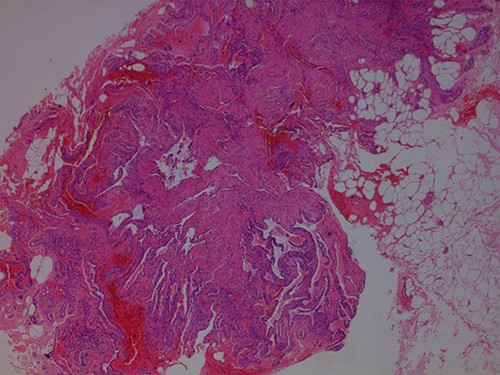

During the procedure tumors were removed completely and subsequently ordered pathological examination confirmed the diagnosis of a GT (Figs 3–5). The report documented the presentation of benign tumors with dilated vessels, surrounded by collars of glomus cells with adjacent hyalinized stroma. The operation was uneventful and on a follow-up visit 6 months later, the patient was completely pain free, with no evidence of local recurrence (Fig. 6). However, a similar lesion was found on the left side of the patient’s lumbar region.

Hematoxylin and Eosin ×100: dilated vessels surrounded by collars of glomus cells with adjacent hyalinized stroma.